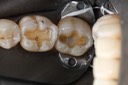

Ted Kanamori #18-19 pre-op